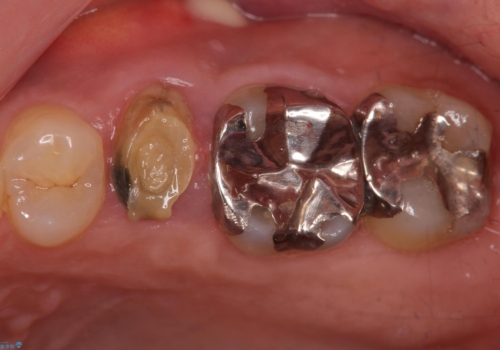

歯茎が腫れる インプラントでの治療

- 40代女性

- 10ヶ月

- 5-10回

- 左上5/インプラント:242,000円 骨増生:55,000円 カスタムアバットメント:110,000円 インプラント用仮歯:22,000円 ジルコニアクラウン:121,000円 合計550,000円費用は治療当時の料金となります